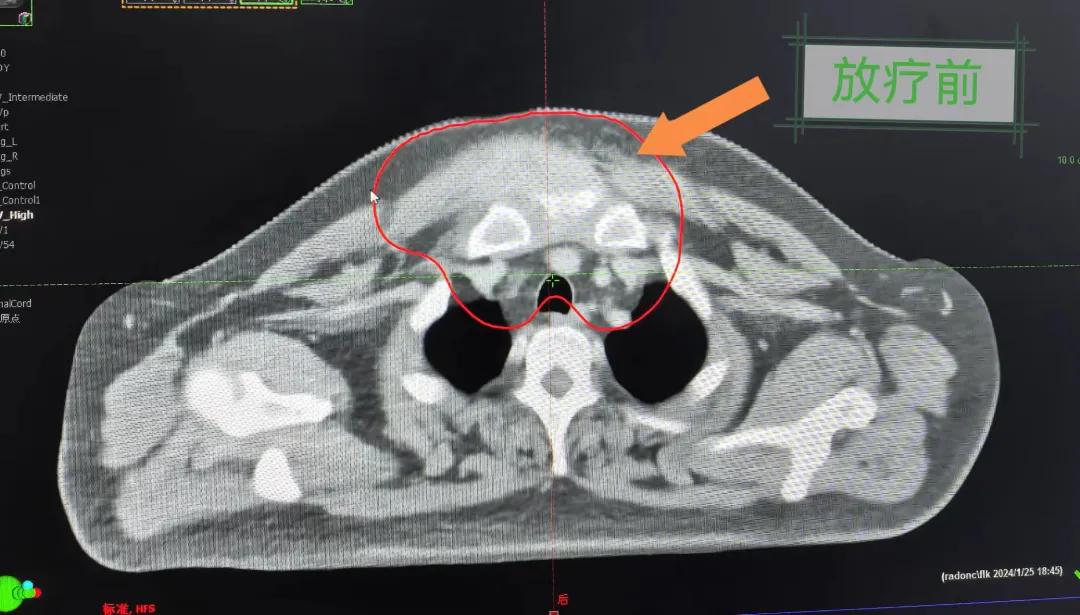

隨后,趙亮主任帶領(lǐng)放療團(tuán)隊(duì)以最快的速度完成了患者的放射治療計(jì)劃,在保證放療精準(zhǔn)打擊腫瘤的同時,利用先進(jìn)的三維立體精確放療技術(shù),最大限度的避免心臟、肺部的損傷發(fā)生,整體治療精準(zhǔn)度達(dá)到1mm以內(nèi)。經(jīng)過10次的放射治療后,患者疼痛已明顯減輕,胸部腫物肉眼可見的縮小,患者及家屬臉上終于露出久違的笑臉。

治療期間,患者沒有出現(xiàn)明顯不適,治療結(jié)束后,患者胸壁腫物由最初8cm縮小至約1cm,后患者至外科行手術(shù)治療。